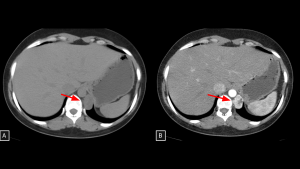

Fig 10: Case 11 – Paravertebral Paraganglioma:

Unenhanced CT (A) reveals a paravertebral mass extending from the retroperitoneum into the thorax. The intense arterial enhancement seen in Panel B is the key diagnostic feature, confirming the tumor's hypervascular nature and distinguishing it from other neurogenic lesions.

SYSTEMATIC APPROACH: 1. Age: Adults (40–50 years; younger in hereditary cases). | 2. Morphology: Highly vascular soft-tissue mass ("Salt-and-pepper" on MRI). | 3. Enhancement: Intense/Avid arterial enhancement. | 4. Relevant Anatomical Relationships: Paravertebral (Sympathetic chain); intense uptake on DOTATATE/MIBG.

Fig 11: Case 12 – Castleman Disease:

Axial CT (A) reveals a right hilar mass with extension to the ipsilateral posterior mediastinum. Coronal view (B) demonstrates the anatomical relationship with the bronchi. The lesion showed uptake on 18 FDG PET CT (C) but remained stable over a 3-year period, consistent with this benign lymphoproliferative disorder.

SYSTEMATIC APPROACH: 1. Age: Young Adults / Adults. | 2. Morphology: Solitary, non-necrotic mass. | 3. Enhancement: Intense homogeneous enhancement (mimicking paraganglioma). | 4. Relevant Anatomical Relationships: Unicentric distribution; often visceral or vascular interface.